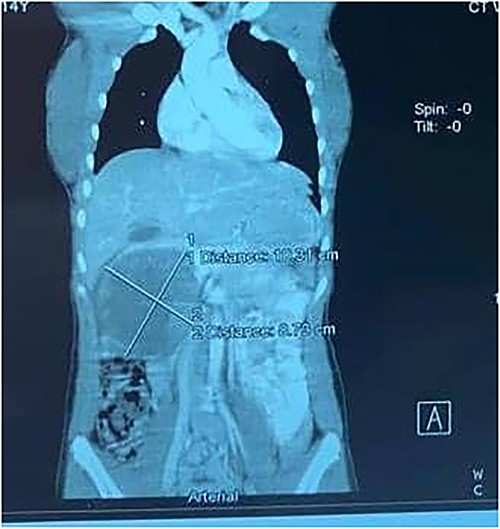

A 21-year-old female collapsed in a market and was taken to a local hospital where she was told that she had a ruptured spleen. She was transfused with two units of whole blood and discharged without surgery. Four weeks later, she noted persistent fullness in her left upper quadrant and presented to our hospital for further evaluation. A contrast CT scan revealed two well-encapsulated, cystic masses in the left upper quadrant, the largest one with small solid components abutting the tail of the pancreas and the smaller one adjacent to the posterior wall of the stomach. She had splenic vein thrombosis, but her portal vein was patent. Numerous portosystemic venous pathways were present, mostly in the gastrosplenic area. The spleen was homogeneous but enlarged with a smooth capsule and normal contour. The liver was normal (Figs. 3 and 4). Her preoperative laboratory studies, including complete blood count, liver function tests, and coagulation studies were normal. A fine-needle aspiration of the anterior mass revealed fresh blood. She was given vaccines against pneumococcus, meningococcus, and haemophilus, anticipating splenectomy would be necessary to resect this mass. At surgery, the splenic artery was ligated at its origin from the celiac axis, which led to an immediate decompression of the peri-splenic and gastric venous collaterals before attempting resection of the mass. The anterior/superior mass was a large, partially organized hematoma, but the inferior mass arose from the tail of the pancreas. A distal pancreatectomy and splenectomy were done en-bloc. The final histopathology revealed a solid pseudopapillary epithelial tumor of the pancreas with negative margins of resection. The patient had an uncomplicated postoperative course and remains asymptomatic.

CT scan showing normal liver and enlarged spleen in close proximity with the mass.